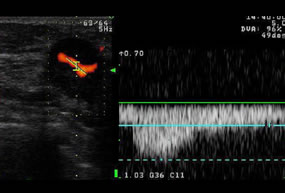

カラードップラー法

血流の方向・速度を画像にすることが出来ます。